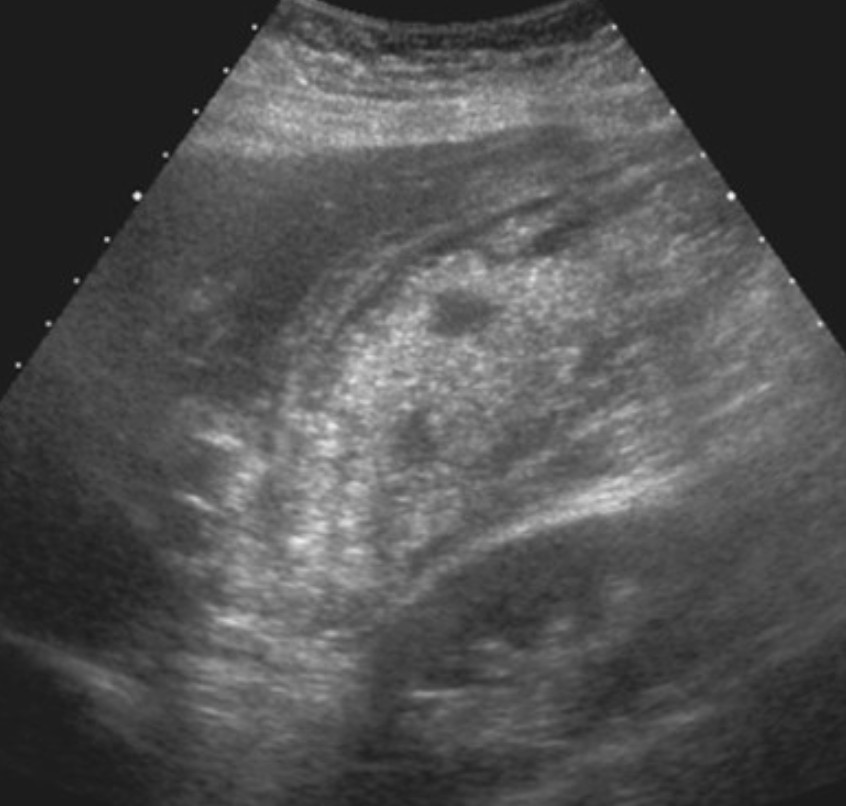

US: thickened bile duct walls +/- debris w/in the biliary system may be present.